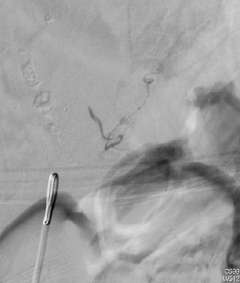

Figure 1: Spinal AVM

Spinal vascular malformation is a very rare condition. It is an abnormal tangle of blood vessels on, in, and/or near the spinal cord (Figure 1).

Depending on where a malformation is located, it is classified as:an intramedullary arteriovenous malformation (AVM within the spinal cord tissue), a pial arteriovenous malformation (AVM on the surface), a dural spinal arteriovenous fistula (DAVF within the membrane that covers the spinal cord), or an epidural arteriovenous fistula (Epidural AVF on the surface of the membrane that covers the spinal cord).

Intramedullary and pial AVMs are considered to be congenital conditions (Figure 1). Larger malformations tend to cause symptoms in a younger age group than smaller AVMs. In fact, smaller malformations can be completely silent. Symptoms from spinal AVMs can occur in a gradual fashion or acutely and dramatically. The symptoms include abnormal sensation in the body, back pain, weakness in the extremities, sexual dysfunction, and bowel/bladder disturbances.